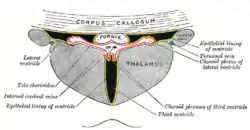

The thalamus is a paired structure of gray matter about four centimetres long, located in the forebrain which is superior to the midbrain, near the center of the brain with nerve fibers projecting out to the cerebral cortex in all directions. The medial surface of the thalamus constitutes the upper part of the lateral wall of the third ventricle, and is connected to the corresponding surface of the opposite thalamus by a flattened gray band, the interthalamic adhesion. The lateral part of the thalamus is the phylogenetically newest part of the thalamus (neothalamus), and includes the lateral nuclei, the pulvinar and the medial and lateral geniculate nuclei.[6][7] There are areas of white matter in the thalamus including the stratum zonale that covers the dorsal surface and the external and internal medullary laminae. The external lamina covers the lateral surface and the internal lamina divides the nuclei into anterior, medial, and lateral groups.[8]

The thalamus has many connections to the hippocampus via the mammillothalamic tract, this tract comprises the mammillary bodies and fornix.[13]